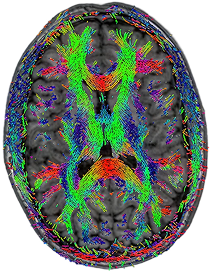

DTI - Tractography

1.5T

3 x 3 x 3mm

5:10

0.5T

10:25

Images from: Halder et al., Investigating the feasibility of resting state functional MRI with GRE EPI on a high performance 0.5 T Scanner, processed using GraphICA, an asset of Brainet-Brain Imaging Solutions Inc.